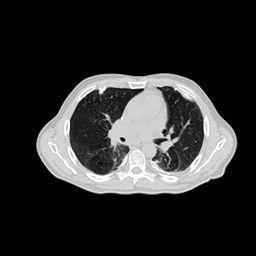

IV-C Few-View CT Reconstruction

In this section, the reconstruction performance of our proposed framework under few-view conditions will be tested. For the parallel and fan beam geometry, the number of views increases from to , uniformly distributing from to and to respectively. Such settings provide a complete benchmark of reconstruction performance, ranging from extremely sparse to relatively complete, full-view CT reconstruction. The experiment results are shown in Fig.5. Additionally, the ground truth, few-view ( views), and full-view ( views) CT reconstruction results of different methods are shown in the first and third rows of Fig.7 (parallel-beam, LIDC-IDRI dataset), and Fig.8 (fan-beam, LIDC-IDRI dataset).

IV-D Limited-Angle CT Reconstruction

To test the proposed framework’s performance on limited-angle reconstruction, we redo the experiment in the above section with the angular range changing from to for parallel-beam geometry and to for fan-beam geometry, one projection per degree. The experiment results are shown in Fig.6. Also, the ground truth and the limited-angle CT reconstruction results of different methods are shown in the row of Fig.7 (parallel-beam, LIDC-IDRI dataset), and Fig.8 (fan-beam, LIDC-IDRI dataset).